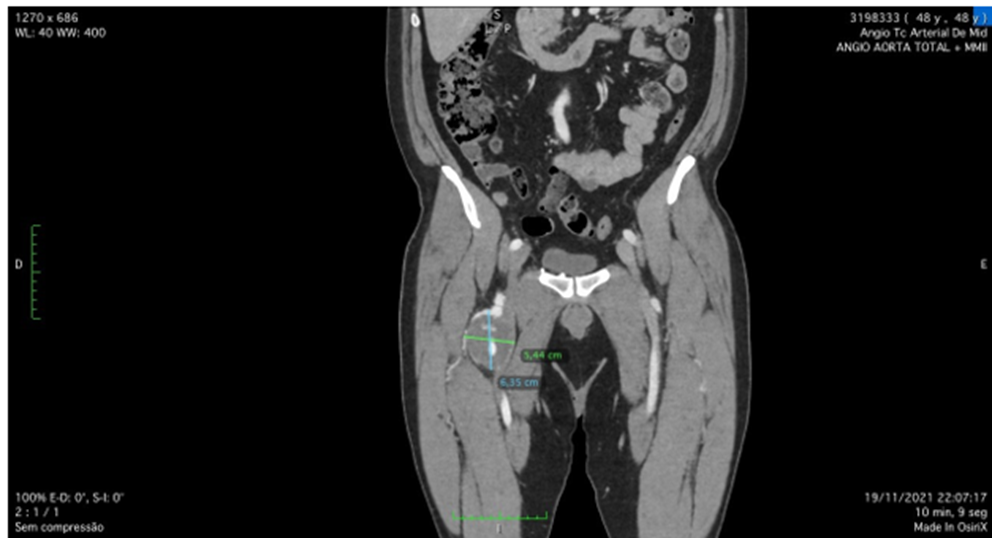

A 49 year-old male patient, with no comorbidities, except for occasional smoking and overweight, was admitted with right limb pain, mainly in the thigh, associated with a weakness and difficulty to walk in the past seven days. The patient was submitted to a duplex ultrasound, that suggested a dilatated deep femoral artery, with 6 cm diameter. On physical examination, he had a good general health, with a pulsating bulge with fibroelastic consistency palpable in the right inguinal region. The patient had femoral, popliteal and distal pulses present bilaterally. The patient was submitted to a duplex ultrasound, that suggested a deep femoral artery aneurysm, with 6 cm diameter. and then. The patient was submitted to a computed tomography angiography (CTA) of the abdomen, pelvis and inferior limbs bilaterally. The CTA showed no other abnormalities in the arterial system, except for an isolated right deep femoral artery aneurysm, with 6,6 cm diameter. (Figures 1 and 2). The distance between the origin of the deep femoral artery aneurysm and the femoral common bifurcation was satisfactory (36,685cm), providing an adequate neck length for endovascular treatment (Figures 2-4). The proximal landing zone had 7,8mm diameter and distal landing zone had 7mm diameter. The total length of the DFAA was 6,85cm. Since there is no consensus in the literature regarding the best way to treat those kind of aneurysms, both techniques, open surgery and endovascular treatment, were extensively explained to the patient. The surgical team and the patient had decided to perform endovascular treatment.

Figure 2: Angio-CT scan showing DFFA